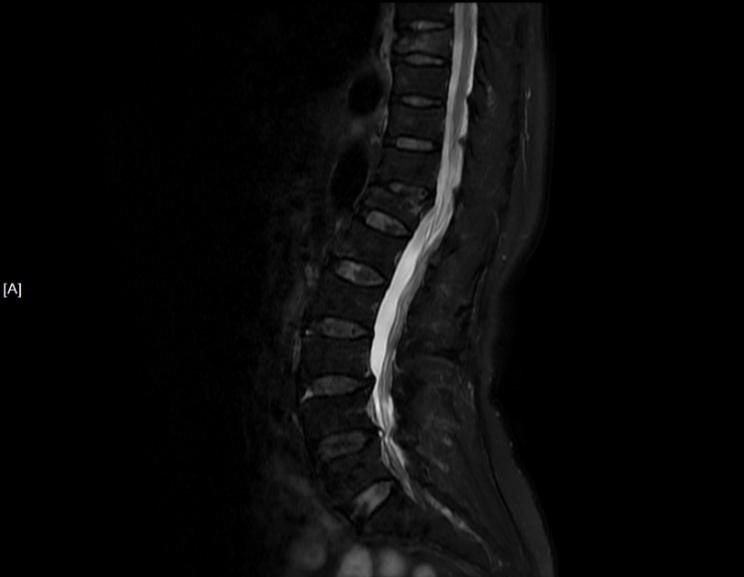

吴老太太今年86岁,同时患有心脏病、老慢支、哮喘、糖尿病等多种疾病,不久前因为并发心衰、呼衰在独墅湖医院经抢救后脱离危险。然而不巧的是,几天前自己在家只轻轻扭了一下腰,就感觉背部疼痛难忍,寝食难安。于是来到我院骨科就诊,医生怀疑是脊柱骨质疏松性骨折,安排收治住院,对病患进行磁共振检查后证实是“第8胸椎压缩性骨折”。

医生在诊断后决定行经皮椎体后突成形术(简称PKP术),需要病人在全身麻醉下俯卧位,医生在全程透视下完成手术。对于一般的患者来说不成问题,而对吴老太太而言却难以实施。首先,她的全身情况较差,心肺功能不全,基础疾病多且严重。入院时就有明显的呼吸困难,氧饱和度只有70%左右,很难耐受全身麻醉。即使勉强度过手术阶段,术后也可能要气管插管,靠呼吸机维持生命,肺部感染则难以控制。其次,如果采用局部麻醉俯卧位手术,尽管可以规避全麻的风险,但该患者根本不能承受俯卧位对心肺功能的影响。但如果不采取手术,卧床以及日夜不停的疼痛对已经遭受过心衰和呼衰的吴老太太来说是雪上加霜。

在常规办法难以实施时,独墅湖医院骨科的医生们决定另辟蹊径,挽救病患生命。常规手术主要面临两大难题:全身麻醉与俯卧位。那么如果采用局部麻醉与侧卧位呢?对!这就是解决问题的关键!局麻可以规避全麻的风险;侧卧可以避免俯卧对心肺的影响。如此,问题似乎迎刃而解了。但是,这样的改变,尤其是侧卧位完成PKP术,导致空间位置变了,手术的难度大大增加了。而且,吴老太太耳背,局麻侧卧位手术需要病人的配合,术中的沟通也是一个问题。尽管困难重重,这也是挽救老人家生命的唯一可行的办法。

科普:骨质疏松性脊柱压缩骨折是中老年人,尤其是绝经后女性的常见疾病,因为激素水平的变化,很容易导致骨质疏松。如果骨质疏松严重的话,轻微的外力或者没有明显外伤的情况下也可能出现骨折,尤其是椎体压缩性骨折,导致患者出现难以忍受的腰背痛,致使患者卧床不起。同时,长时间的卧床会使老年人身体状况迅速恶化,部分患者甚至可能因此而失去生命。目前临床上解决这一难题的最佳方法是椎体强化术(一种微创手术),通俗来说就是向骨折椎体里注入骨水泥(一种医用固化剂),骨折的椎体迅速得到强化,术后疼痛立即缓解,术后即可下地行走,效果立竿见影。